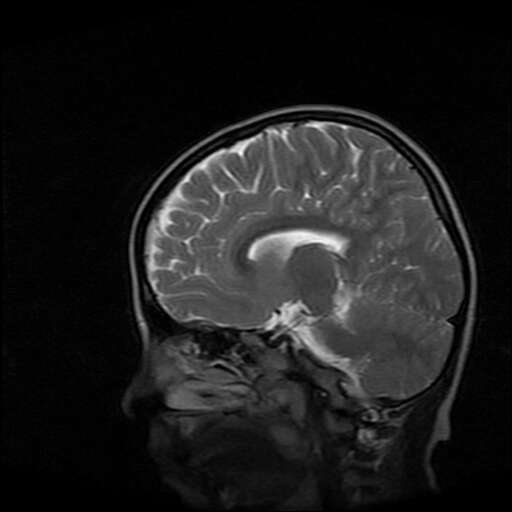

女,7岁,三岁才说话、走路。现智力尚可,走路不稳。临床怀疑大脑发育不全。

考虑胼胝体发育不全,髓鞘形成不良。

支持考虑胼胝体发育不全,髓鞘形成不良。

脑裂畸形伴灰质异位

侧脑室周围白质数量减少,侧脑室不对称性扩大,左侧侧脑室后角呈方形改变,脑沟加深,结合临床考虑脑室周围白质软化症(pvl)。期待结果!